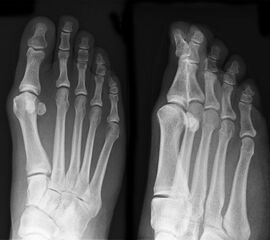

• Die Operationsplanung erfolgt anhand der Röntgenaufnahmen des Vorfußes unter Belastung in 2 Ebenen. Für die Verfahrenswahl sind wichtig der Intermetatarsalwinkel und die Breite des Os metatarsale, der Hallux valgus Winkel, der distalen Gelenkflächenwinkels (Distal Metatarsal Articular Angulation - DMAA), des Metatarsaleindex und Sesambeinposition (Abb. 1).

• Mittelgradige bis schwere Hallux valgus Fehlstellung (Intermeterversalvinkel ab ca. 15°)

• Bei hohem Hallux valgus Winkel oder pathologischem Gelenkflächenwinkel besteht die Indikation zu einer zusätzlichen Isham Osteotomie 2, die im Wesentlichen der offenen Reverden Green Osteotomie entsprecht.